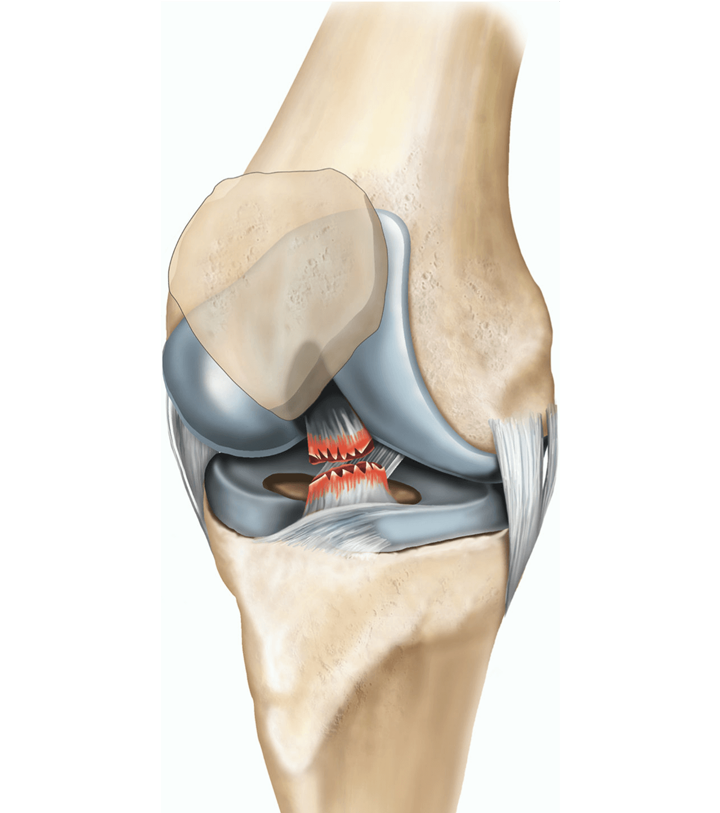

The anterior cruciate ligament (ACL) plays a vital role in stabilising the knee, particularly during activities involving sudden changes in direction, jumping, and running. ACL reconstruction is a surgical procedure aimed at repairing or replacing a torn ACL, typically caused by sports-related injuries or trauma. This procedure is essential for restoring knee stability, reducing pain, and allowing patients to return to their previous level of activity.

ACL reconstruction involves the replacement of a damaged or torn ACL with a graft, typically taken from the patient’s own tendon (autograft) or from a donor (allograft). The goal of the procedure is to restore the function of the knee, reduce the risk of further joint damage, and help the patient return to normal activities such as sports or physical exercise.

- ACL Removal: The damaged ACL is removed, and the area is cleaned to prepare for the new graft.

- Graft Placement: The graft is carefully positioned and attached to the femur and tibia with screws or other fixation devices.